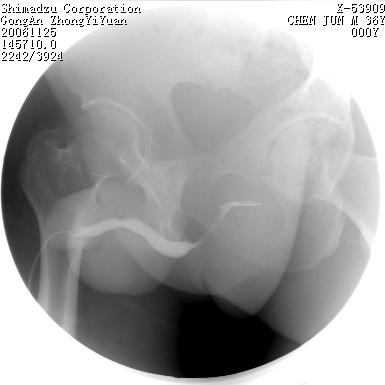

男 66岁 排尿困难半年;此人腹腔及腹膜后积液.

尿道充盈缺损,考虑占位.

后尿道内充盈缺损;前列腺结石。

后尿道狭窄,其中可见充盈缺损,我认为应先排除结核.

后尿路精阜水平充盈缺损,考虑结石或占位病变可能,建议mri检查,精阜水平尿路周围条索状密度增高影,考虑造影剂逆流入输精管或周围静脉。